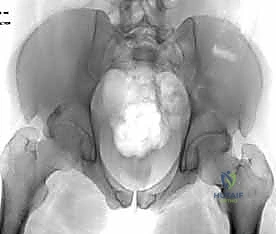

عند حدوث قوة قاهرة تفوق قدرة تحمل هذه الأربطة، يتمزق المفصل وتنفصل عظام العانة عن بعضها، وهو ما يُعرف طبياً بـ "كسر الكتاب المفتوح" (Open Book Fracture) إذا تجاوز الانفصال 2.5 سم. هذا الانفصال يؤدي إلى عدم استقرار كامل في الحلقة الحوضية.

يتم تقييم المريض بشكل شامل (أشعة سينية، أشعة مقطعية ثلاثية الأبعاد) لتحديد حجم الإصابة بدقة. تُجرى العملية تحت التخدير العام لضمان استرخاء العضلات بالكامل وعدم شعور المريض بأي ألم. يتم وضع المريض على ظهره على طاولة العمليات، وتُعقم منطقة البطن والحوض بالكامل.

بمجرد استعادة الوضع الصحيح للعظام، يقوم الدكتور هطيف بتثبيتها باستخدام صفيحة معدنية متخصصة (غالباً صفيحة إعادة بناء متعددة الثقوب مصنوعة من التيتانيوم أو الفولاذ المقاوم للصدأ الطبي). يتم تثبيت هذه الصفيحة عبر المفصل العاني باستخدام مسامير قشرية (Cortical Screws) تُغرس بعمق في عظام العانة الصلبة لضمان تثبيت قوي يتحمل ضغط الجسم.